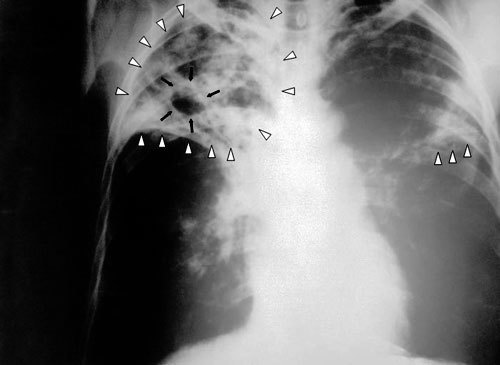

Гуманитарная организация "Международный медицинский корпус" подвела итоги работы на Северном Кавказе за 2009 год. Врачи отмечают, что в регионе растет заболеваемость туберкулезом и ВИЧ, а лечебно-профилактические учреждения в достаточном объеме отсутствуют.

Рост заболеваемости туберкулезом на Северном Кавказе практически самый высокий в России

"Рост заболеваемости туберкулезом на Северном Кавказе практически самый высокий в России. В Чечне как уже зарегистрированных, так и новых случаев больше, чем в любом другом регионе России за исключением тех, где находятся учреждения пенитенциарной системы, в частности, в некоторых регионах Сибири", - рассказал корреспонденту "Кавказского узла" руководитель российского отделения ММК Семен Расин.

По данным "Международного медицинского корпуса", сегодня в Чечне туберкулезом заражено 355 человек на сто тысяч населения. Выше этот показатель только в Кемеровской области (377 человек). Близки к "лидерам" Ингушетия (240 человек) и Северная Осетия (225 человек). Для сравнения: в Москве этот показатель составляет 77 человек.

По данным врачей, сегодня в Чечне около 5 000 зарегистрированных больных туберкулезом. По словам Семена Расина, официальные цифры заболеваемости отражают лишь часть реальности. "Уровень заболеваемости туберкулезом очень значительный, причем уровень его выявляемости крайне низок. Очень плохой уровень подготовки специалистов. Есть энтузиасты, которые пытаются что-то сделать. А вот квалифицированных специалистов на местах практически нет - никто не хочет ехать работать в Чечню", - сетует руководитель российского отделения ММК.

На вопрос, в чем причины роста числа людей, больных туберкулезом, Семен Расин отвечает так: "Во время войны в Чечне не было никаких лекарств вообще. Все больные, которые находились на лечении от туберкулеза, перестали его получать, заражая при этом остальных. Во-вторых, туберкулез - болезнь социальная, болезнь бедности. Уровень безработицы в Чечне достигает 70% населения, а безработица среди молодежи - 85%".